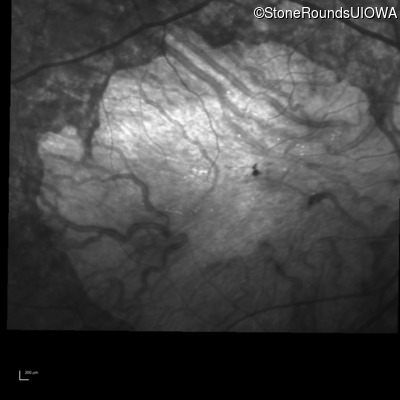

Infrared Fundus Photograph - Right - 10/200 sc

Exemplar